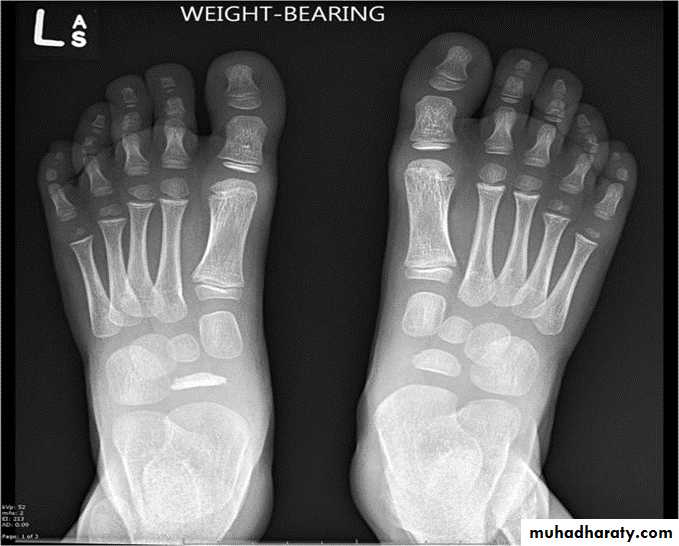

GOUT

Heterogeneous group of entities characterized by recurrent attacks of arthritis secondary to deposition of sodium urate crystals in and around joints.

Radiographic features:

Lower extremity > upper extremity; small joints > large joints

* First MTP is most common site

* Marginal, peri articular erosions: overhanging edge

* Erosions may have sclerotic borders

* Joint space is preserved

* Soft tissue and bursa deposition

Tophi: juxtaarticular, helix of ear

* Tophi calcification, 50%

*Chondrocalcinosis